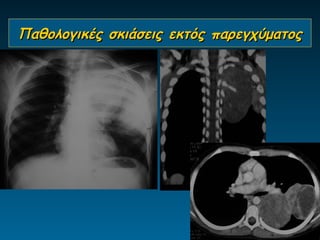

Παθολογικές σκιάσεις εκτός παρεγχύματος